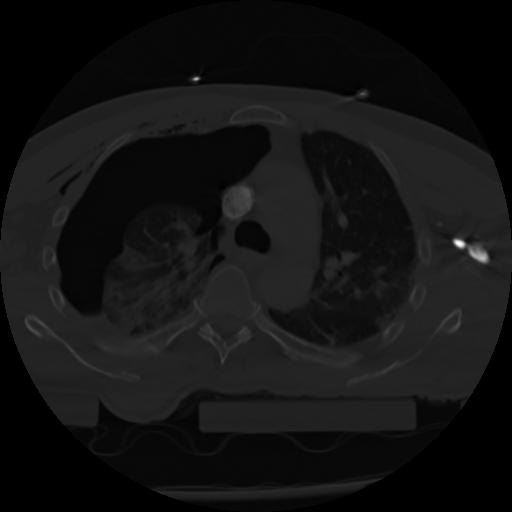

21 ANGIO,CE,Axial,3.0,ANGIO,,